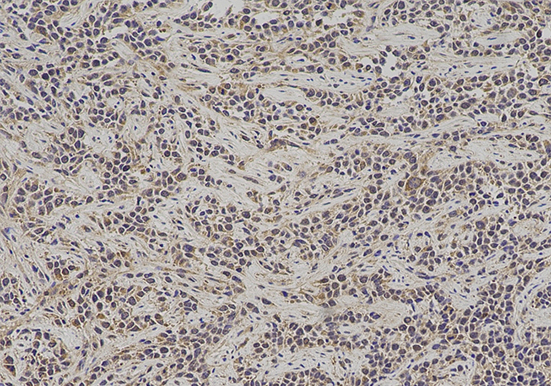

实验结果展示:

技术原理免疫组化,是应用免疫学基本原理——抗原抗体反应,即抗原与抗体特异性结合的原理,通过化学反应使标记抗体的显色剂(荧光素、酶、金属离子、同位素)显色来确定组织细胞内抗原(多肽和蛋白质),对其进行定位、定性及定量的研究,称为免疫组织化学技术(immunohistochemistry)或免疫细胞化学技术(immunocytochemistry)。

免疫组化,是应用免疫学基本原理——抗原抗体反应,即抗原与抗体特异性结合的原理,通过化学反应使标记抗体的显色剂(荧光素、酶、金属离子、同位素)显色来确定组织细胞内抗原(多肽和蛋白质),对其进行定位、定性及定量的研究,称为免疫组织化学技术(immunohistochemistry)或免疫细胞化学技术(immunocytochemistry)。